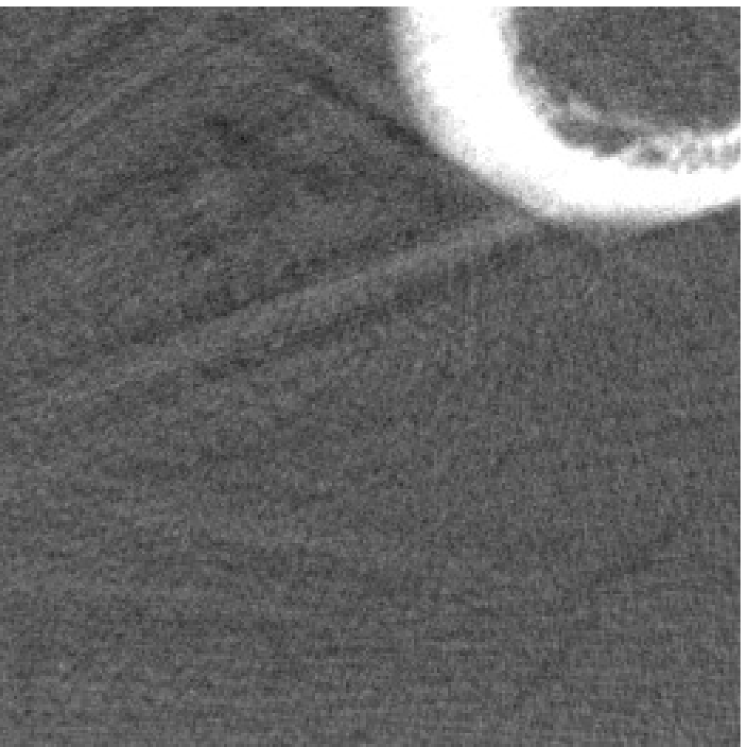

The optimization problem (2.12) can be solved by the split Bregman algorithm [29, 8] efficiently, which is also equivalent to the alternating direction method of multipliers (ADMM) [24, 26, 28]. The reconstructed phantom image by model (2.12), denoted by , is shown in Figure 1(b). Metal location in image domain can be robustly estimated by the summation of the high frequency wavelet frame coefficients (Figure 1(c)) followed by a simple thresholding. Then, the index of the metal trace in Radon domain, denoted by , can be identified by the projection of the indicator function associated to the metal location (Figure 1(d)).

Note that one may estimate the metal location by simply thresholding the initially reconstructed image. However, the metal artifacts may have a significant influence on the estimation if the threshold is not properly chosen. Thanks to the multiscale structure of the wavelet frame transform, we are able to robustly detect features from poorly reconstructed images based on the summation of high frequency tight framelet coefficients. This has already been observed in the past [18, 7]. In Table 1, we show that the quality of the reconstructed image using the proposed re-weighted JSR model is not very sensitive to the choice of the threshold (denoted by ) on the summation of high frequency tight framelet coefficients. Furthermore, the proposed approach is better than directly thresholding on the initially reconstructed image.